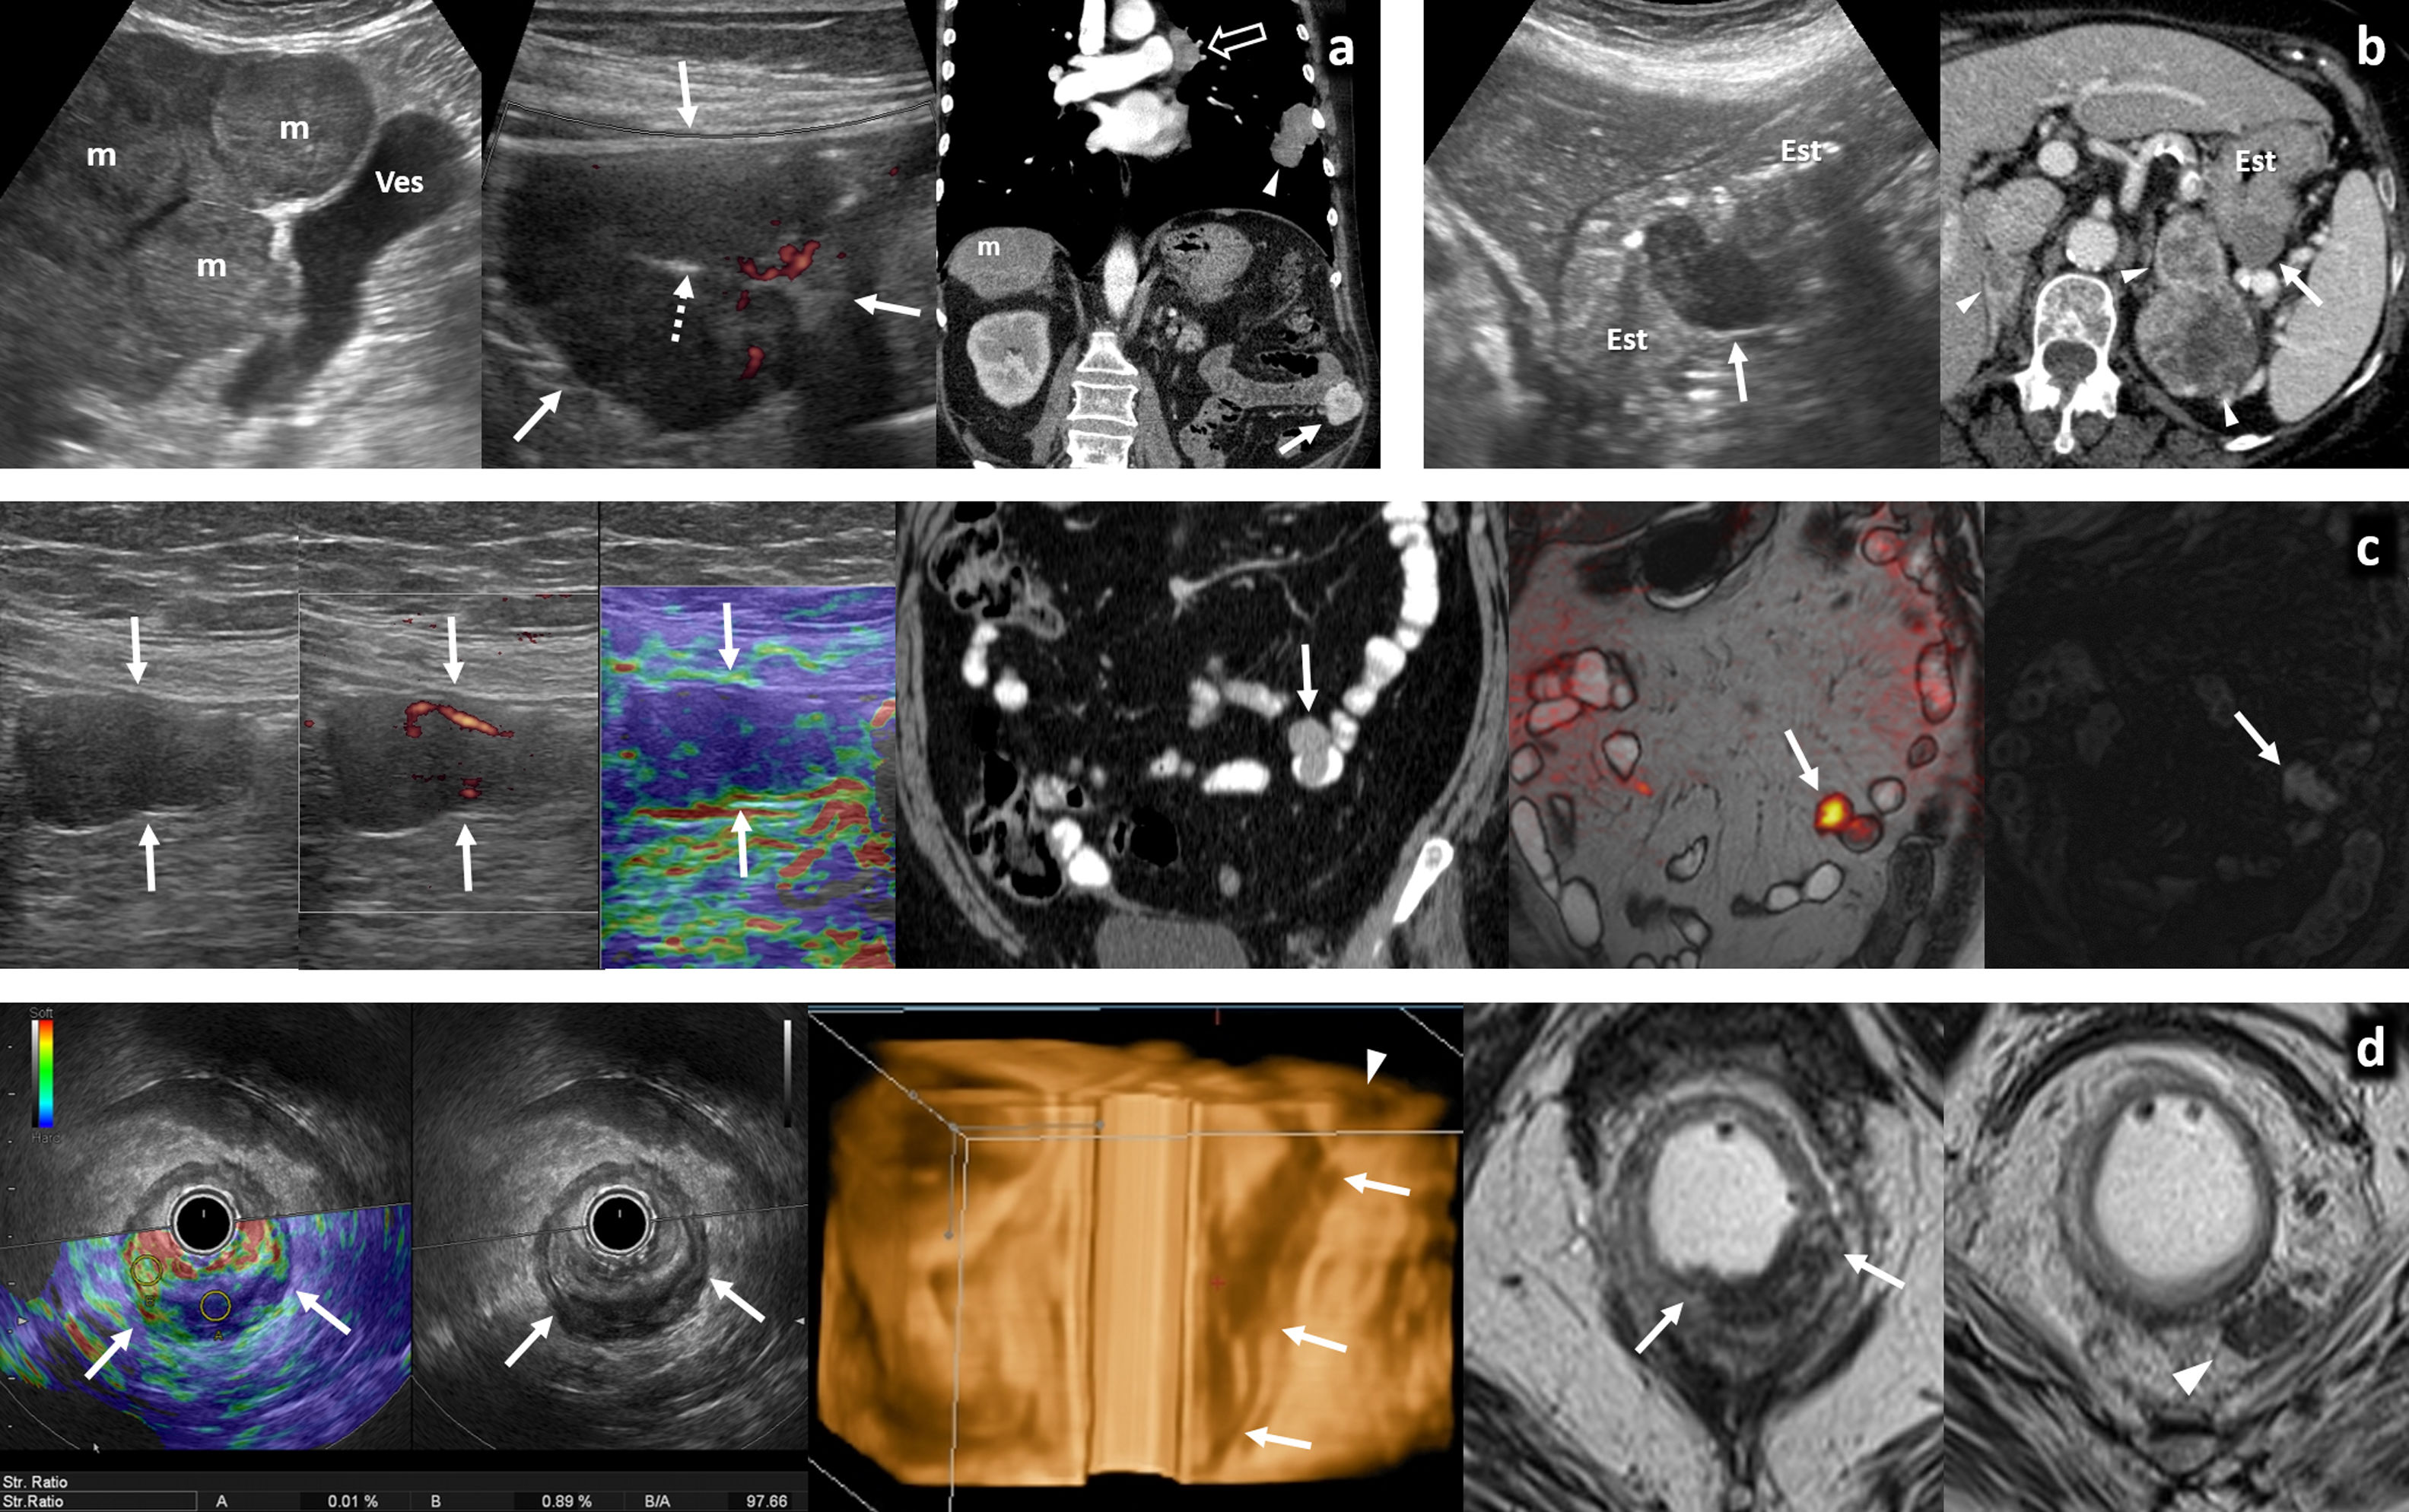

Tumores hematológicos (fig. 7)Aunque infrecuentes (1-8%), el tracto gastrointestinal supone el asiento extraganglionar más habitual del linfoma, casi siempre no Hodgkin-B, primario o secundario. El orden de frecuencia de afectación es estómago, intestino delgado (especialmente íleon distal), colon-recto y esófago. Ecográficamente suele presentarse como masa o, más habitualmente, un engrosamiento mural circunferencial hipoecogénico marcado, más homogéneo, largo y menos obstructivo que el carcinoma, en ocasiones preservando relativamente la estructura en capas. Puede ser multifocal, ulcerarse, cavitar y, por destrucción del plexo mioentérico, producir dilatación aneurismática de la luz. Suele acompañarse de adenopatías hipoecogénicas prominentes, y a veces de afectación peritoneal o de otros órganos. Con contraste muestra realce homogéneo, más discreto y tardío que otros tumores36,59,60.

Linfomas gastrointestinales. A) Linfoma difuso de células grandes de íleon terminal. Mujer de 36 años. Imagen izquierda: tomografía computarizada (TC) coronal con contraste oral e intravenoso. Imagen derecha: ecografía. Engrosamiento mural hipoecogénico e hipovascular marcado en un tramo largo de íleon distal (flechas) cuya luz se encuentra dilatada (*). Se acompaña de una masa mesentérica adyacente de ecogenicidad similar (cabezas de flecha), sobre la que se realizó BAG guiada ecográficamente (flechas huecas). B) Linfoma difuso de células grandes de yeyuno distal. Varón de 70 años. Imagen superior: TC coronal con contraste oral e intravenoso. Imagen inferior: ecografía. Engrosamiento mural hipoecogénico e hipovascular marcado en un tramo más corto de yeyuno distal (flechas), también con dilatación aneurismática (*) y una masa mesentérica adenopática acompañante (cabeza de flecha). El diagnóstico se consiguió con la biopsia percutánea del engrosamiento intestinal (no mostrado). C) Enfermedad inmunoproliferativa de intestino delgado (o “linfoma mediterráneo”, subtipo de linfoma extranodal de la zona marginal). Varón de 17 años con diarrea, fiebre y dolor abdominal. La ecografía muestra adenopatías mesentéricas homogéneas (cabezas de flecha), engrosamiento de pliegues de yeyuno proximal (flechas), con una invaginación larga de yeyuno (flechas discontinuas) con mesenterio en su interior (m), así como pequeñas lesiones focales hepáticas hipoecogénicas (flechas huecas). El diagnóstico se obtuvo con la biopsia de dos lesiones focales hepáticas (no mostrado). D) Linfoma T gástrico de alto grado asociado a enteropatía. Varón de 61 años con diagnóstico de enfermedad celiaca. Imagen superior: TC. Imagen inferior: BAG guiada ecográficamente. Engrosamiento circunferencial hipovascular e hipoecogénico (no mostrado) de antro gástrico (flechas), con múltiples lesiones focales hepáticas hipocaptantes (cabezas de flecha) y levemente hipoecogénicas. En la gastroscopia se ve una lesión antral ulcerada, pero las biopsias son repetidamente negativas. El diagnóstico se consigue con la biopsia percutánea de las lesiones hepáticas. E) Linfoma folicular de bajo grado de yeyuno proximal. Varón de 73 años. Imagen izquierda: TC axial (superior) y coronal MIP fino (inferior). Imagen derecha: ecografía, corte transversal (superior) y biopsia percutánea. Engrosamiento mural excéntrico de un tramo de yeyuno proximal (cabezas de flecha) con una gran masa mesentérica (flechas) que se extiende hasta el ángulo de Treitz (t), con escaso efecto de masa sobre los vasos mesentéricos a su través. a: aorta. Ecográficamente se define mejor la heterogeneidad de este conglomerado adenopático, lo que permite dirigir la biopsia percutánea a la parte más sólida de la masa mesentérica (flechas huecas). Persiste en remisión completa tras 3 años de iniciar la quimioterapia. F) Linfoma de Burkitt ileocecal. Mujer de 46 años. Imagen izquierda: ecografía. Imagen derecha: TC coronal. Engrosamiento mural importante, excéntrico, en la región ileocecal (flechas) sin estenosis de la luz (*) y con cierta sensación de preservación de la estructura ecográfica en capas a pesar de la magnitud del engrosamiento. Se acompaña de un conglomerado adenopático mesentérico (cabezas de flecha) que se define con más precisión en la ecografía, así como numerosas lesiones focales hepáticas (flechas discontinuas) y ascitis (+). Persiste en remisión completa tras 4 años de iniciar la quimioterapia. G) Linfoma de células del manto de alto grado con afectación de ángulo esplénico del colon. Mujer de 69 años. Imagen izquierda: TC coronal. Imagen derecha: ecografía. Gran masa que engloba el ángulo esplénico del colon (c) y se extiende hacia su meso (flechas). Se acompaña de afectación de íleon distal (i), vesícula (v) y útero (u) como engrosamiento visceral, así como adenopatías mesentéricas (cabezas de flecha), ascitis (+) y linfomatosis peritoneal (flechas discontinuas). El diagnóstico se obtuvo con biopsia percutánea ecodirigida de la masa del mesocolon (flechas huecas).

GIST y otros tumores mesenquimales (fig. 8)El GIST, derivado de la célula intersticial de Cajal, es ampliamente la neoplasia mesenquimal gastrointestinal más frecuente, asentando generalmente en la capa muscular. Aproximadamente el 60% afectan al estómago, el 30% al intestino delgado y el 4% al colon-recto. La edad media al diagnóstico es de 60 años, menor en contextos sindrómicos (síndrome de Carney-Stratakis, tríada de Carney, neurofibromatosis-1) en los que los principios ALARA cobran especial relevancia62.

GIST gastrointestinales. A) Múltiples GIST gástricos en el contexto de síndrome de Carney-Stratakis. Se sumaban varios paragangliomas cervicales (no mostrado). Mujer de 20 años. De izquierda a derecha: ecografía (corte transversal en epigastrio), tomografía computarizada (TC) axial con contraste oral e intravenoso en el mismo plano y TC coronal. Hay innumerables nódulos y masas sólidos (*) de ecogenicidades diversas, dependientes de la pared gástrica. En algunos se aprecian focos de degeneración quística o necrótica (+). a: aorta. No hubo respuesta a imatinib y requirió gastrectomía subtotal. No había mutación en c-KIT ni PDGFRA y sí mutación germinal en una subunidad de SDH (habitual en estos casos). Los GIST en síndromes afectan más a mujeres jóvenes y niñas, con subtipo histológico más frecuentemente epitelioide que fusocelular. Frecuentemente aparecen como múltiples tumores gástricos, con adenopatías menos excepcionales y más rara respuesta a imatinib que los esporádicos. B) GIST gástrico pequeño con crecimiento endofítico. Varón de 71 años. De izquierda a derecha: ecografía (corte transversal en epigastrio), ecografía con contraste y TC axial sin contraste (antecedente de reacción adversa grave). Hallazgo ecográfico incidental de tumor lobulado homogéneamente hipoecogénico (*) con crecimiento endofítico en el antro gástrico. Pese a ser un estudio con sonda convexa de baja frecuencia en paciente obeso, se puede apreciar cómo la lesión depende de la capa muscular propia, encontrándose inmediatamente superficial a la capa submucosa ecogénica más proximal. Las flechas señalan a la luz gástrica. En ecografía con contraste la lesión realza de forma rápida y homogénea, con lavado posterior. Ciertos equipos y PACS permiten un análisis cuantitativo. En TC sin contraste la lesión pasa prácticamente desapercibida. C) GIST gástrico con crecimiento exofítico y complicación hemorrágica espontánea. Mujer de 82 años. Dolor abdominal y anemización. De izquierda a derecha: ecografía (corte transversal en hipocondrio derecho), ecografía con contraste y TC coronal con contraste. Masa heterogénea (flechas) con crecimiento exofítico desde el antro gástrico (cabezas de flecha) y una ulceración (flecha discontinua). Líquido peritoneal (*) con finos ecos y denso en TC basal (no mostrado). En ecografía con contraste hay realce intenso y rápido, con lavado tardío. En la periferia de la masa no hay realce (+). En TC corresponde a coágulo centinela. En la cirugía se encontró hemoperitoneo y se resecó un GIST gástrico sangrante. D) GIST ileal ulcerado con crecimiento exofítico. Varón de 66 años con melenas. Imagen izquierda: ecografía. Imagen derecha: TC coronal con contraste oral e intravenoso. Recuadro: biopsia con guía ecográfica (flechas huecas). Masa lobulada de ecogenicidad intermedia creciendo exofíticamente desde íleon proximal (flechas), con ulceración mucosa (flechas discontinuas). E) GIST colónico hemorrágico. Varón de 72 años. Imagen izquierda: ecografía (corte longitudinal en hipogastrio). Imagen derecha: TC axial con contraste. Gran masa heterogénea (flechas), con amplias áreas necróticas (+), una burbuja de gas intralesional por cavitación (flecha discontinua) y hemoperitoneo (*). Dependía del colon sigmoide distal. F) GIST rectal pequeño. Imagen izquierda: ecografía transrectal con Doppler. Imagen derecha: resonancia magnética sagital T2 con gel endorrectal. Recuadro central: elastografía de strain. Lesión nodular homogéneamente hipoecogénica en la cara anterior del recto inferior (*), con alta rigidez tisular en elastografía cualitativa. La ecografía demuestra su dependencia de la capa muscular propia hipoecogénica (flechas). u: útero miomatoso.

Son tumores hipoecogénicos circunscritos, redondeados o lobulados, generalmente con crecimiento exofítico no infiltrante, con frecuentes áreas de degeneración quística, hemorrágica o necrótica (hipo-anecoicas) cuando son grandes. Pueden presentar calcificaciones, ulcerarse y sangrar al intestino o al peritoneo. Tienden a metastatizar al peritoneo (también como tumores redondeados) y el hígado, siendo excepcionales las adenopatías. Diversos sistemas de estadificación pronóstica consideran aspectos radiológicos (tamaño, heterogeneidad, ulceración, localización, intensidad y patrón de realce) y no radiológicos (índice mitótico, subtipo histológico, diferenciación, pleomorfismo, rotura quirúrgica)35,36,63,64.

Las áreas sólidas realzan intensamente con contraste ecográfico, que también permite guiar la biopsia y muestra potencial como marcador pronóstico y en el seguimiento en pacientes tratados con imatinib64,65. El realce intenso y heterogéneo permite además diferenciarlo del leiomioma (mucho más frecuente en el esófago) y otros tumores mesenquimales benignos, que morfológicamente pueden ser semejantes, pero tienden a realzar menos y homogéneamente35,65–67. Es más dudoso si los GIST son significativamente más rígidos que los leiomiomas en elastografía ecoendoscópica66,68. Los lipomas suelen ser hiperecogénicos29. Los tumores mesenquimales malignos no son diferenciables del GIST por imagen.

Metástasis (fig. 9)Las más frecuentes son de melanoma, carcinoma pulmonar y renal29,59. Es discutible la existencia del melanoma intestinal primario69. Se comportan como nódulos submucosos hipoecogénicos a veces múltiples, ocasionalmente con infiltración circunferencial, crecimiento endoluminal o ulceración. Es clave conocer el antecedente oncológico.

Metástasis intestinales. A) Metástasis yeyunal ulcerada de tumor neuroendocrino pulmonar. Varón de 65 años. Síndrome constitucional. De izquierda a derecha: ecografía hepática, ecografía en flanco izquierdo y tomografía computarizada (TC) coronal con contraste. Tumor pulmonar primario (cabeza de flecha), adenopatías mediastínicas (flecha hueca), metástasis hepáticas (m) y metástasis yeyunal hipoecogénica e hipervascular (flechas), con una ulceración (flecha discontinua). B) Metástasis gástrica de carcinoma de células claras renal. Mujer de 72 años. Imagen izquierda: ecografía longitudinal en epigastrio. Imagen derecha: TC axial con contraste. Metástasis hipoecogénica lobulada (flechas) en la pared posterior del cuerpo del estómago (Est). Hay también metástasis adrenales (cabezas de flecha), cardiacas, peritoneales, óseas y de partes blandas (no mostradas). C) Metástasis yeyunal endo- y exofítica de melanoma lentiginoso acral. Mujer de 56 años. De izquierda a derecha: ecografía en vacío izquierdo, eco-Doppler, elastografía de strain, TC coronal con contraste oral e intravenoso, entero-RM fusión difusión-T2 coronal, T1 coronal sin contraste. Metástasis lobulada, con un componente endofítico y otro exofítico en un tramo de yeyuno (flechas). Es hipoecogénica, moderadamente vascularizada, rígida en elastografía, homogénea en TC, con restricción de la difusión y moderadamente hiperintensa en T1 por contenido en melanina. D) Melanoma anorrectal. Mujer de 64 años. De izquierda a derecha: elastografía de strain y ecografía transrectal en recto inferior, reconstrucción 3D de ecografía endorectal, RM T2 axial en un plano más inferior y más superior. Lesión infiltrante en la pared posterior de recto inferior y ano con gran rigidez tisular (strain ratio de 97,66), con asiento en submucosa e infiltración de mucosa y transmural (flechas), así como adenopatías perirrectales (cabezas de flecha). También había invasión de venas extramurales y metástasis hepáticas (no mostradas). No se encontró melanoma cutáneo.